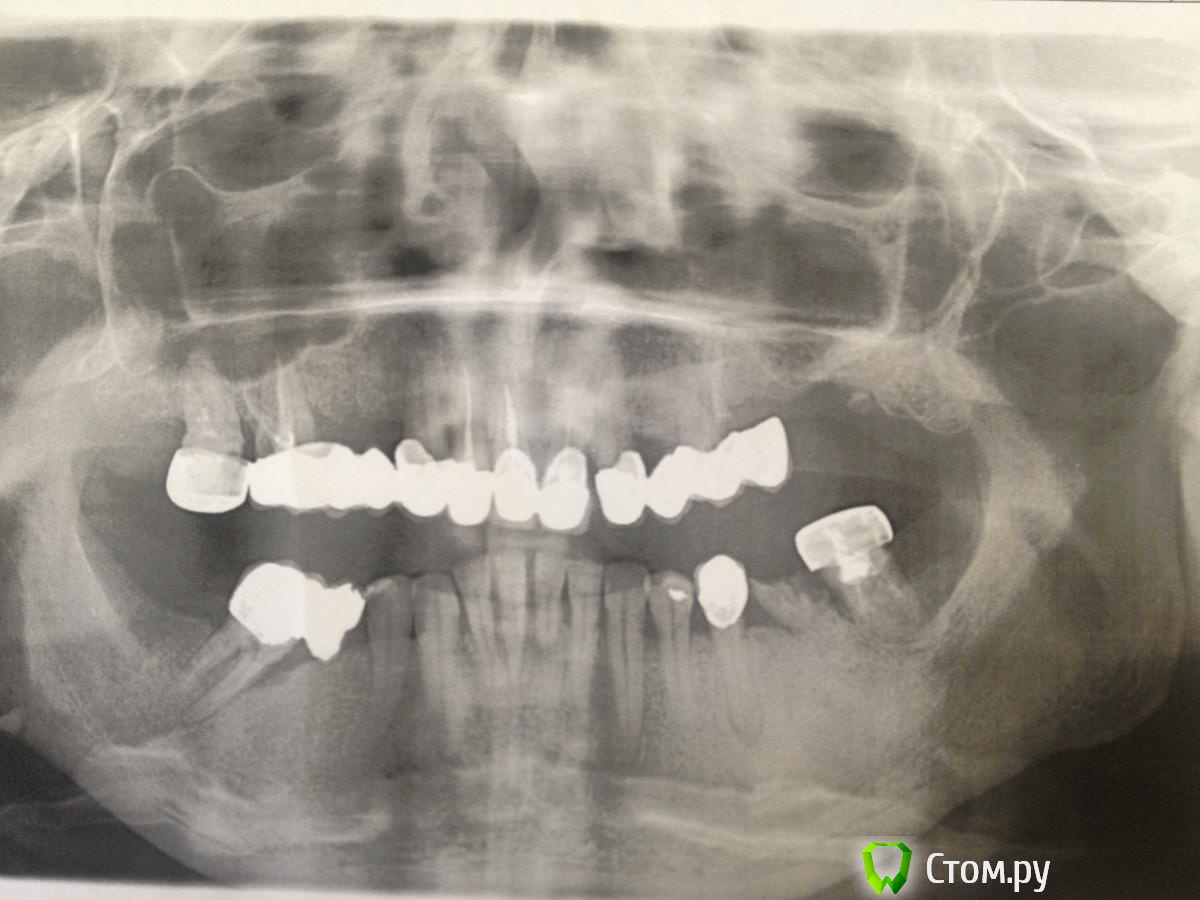

Beznika Опубликовано 13 февраля, 2014 Поделиться Опубликовано 13 февраля, 2014 Жесть Для начала чистку назначьте Что там с 37? или 36... Ссылка на комментарий

Beznika Опубликовано 13 февраля, 2014 Поделиться Опубликовано 13 февраля, 2014 Консольку на стороне 4. Снять придётся походу , а то зуб поехал ))) Ссылка на комментарий

MaxDok Опубликовано 13 февраля, 2014 Автор Поделиться Опубликовано 13 февраля, 2014 Пациентка перезаписалась , пуржило у нас , завтра снимаю конструкцию с вч,примерю мокап, 36 на удаление. Ссылка на комментарий

Im@m Опубликовано 14 марта, 2014 Поделиться Опубликовано 14 марта, 2014 Пациент, 45 лет. Жалобы на эстетически не состояельные реставрации . Хочет красивую улыбку С чего посоветуете начать коллеги?1. проф гигиена 2. Снять все мосты3. КТ+ КПЛ(комплексный план лечения) +КДМ(контрально-диагностические модели в окклюзии)4. удаление Ссылка на комментарий